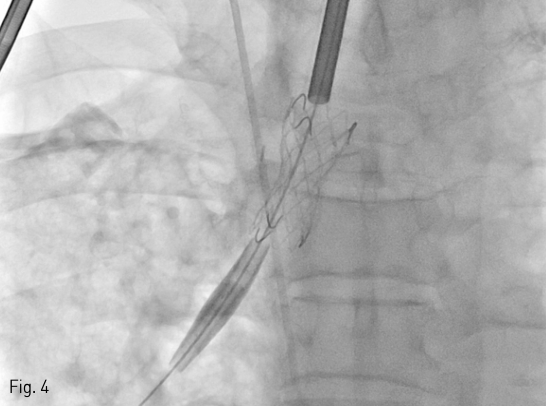

수술 3주 후에 시행한 흉부 CT에서 수술부위의 bronchial stump에 작은 틈새가 보였다 (Fig. 1). 그로부터 11일 뒤 시행한 CT에서 stump의 틈새가 더욱 커지고 (axial dimension: 8 mm) 흉강과 교통을 보이는 기관흉막루가 형성되었다 (Fig. 2).

Fig 2

In the follow-up CT taken 11 days later, the defect of the bronchial stump (white arrow) has enlarged significantly.